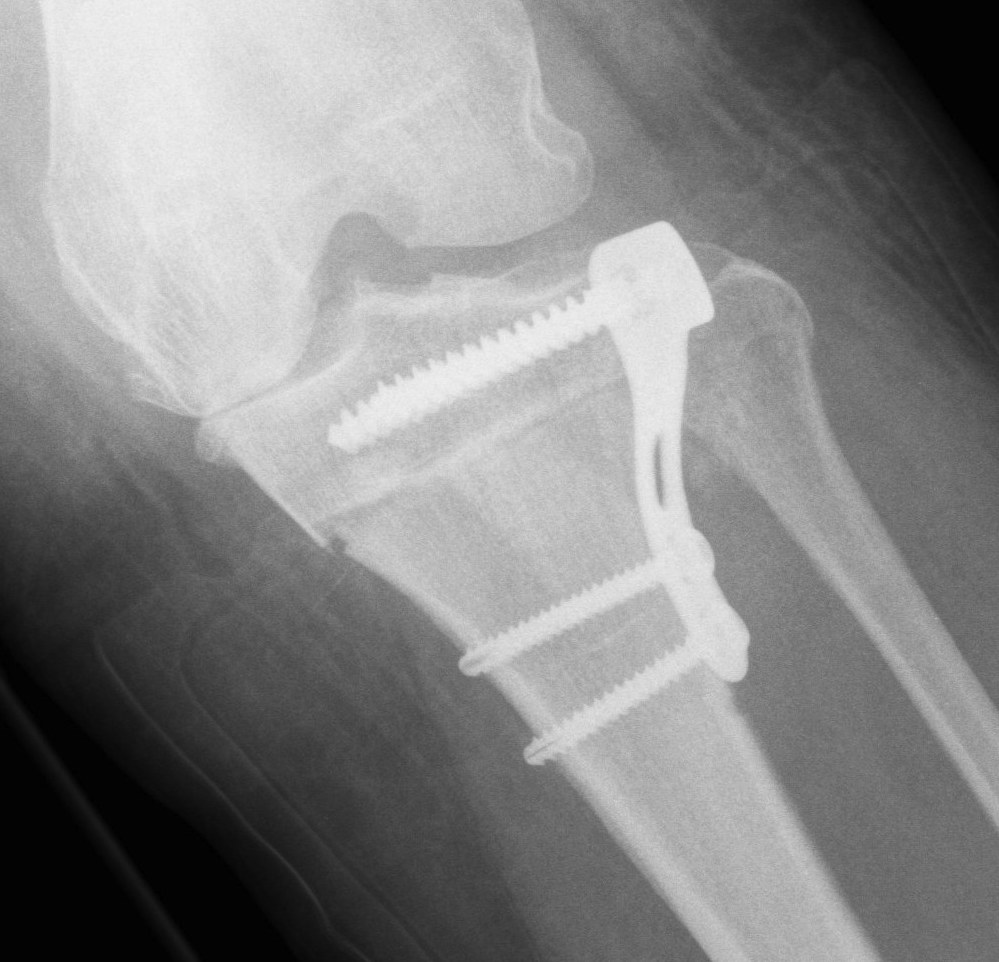

Stabilise osteotomy with plate